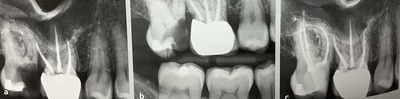

左の歯、6番、第一大臼歯の根管治療をして欲しいと紹介された方。

根っこがV字、二股に分かれていますが、右の奥側の根っこには歯が充分に残ってます。

が、手前は下の骨近くまで虫歯が進んでいます。

白いセメント?みたいな詰め物がされてますが、深くて左右に根っこがバラバラになりそうです。

で、被せられましたが、長持ちするのかは?疑問です。

歯周病の検査、ポケットの深さや歯ぐきの状態を調べるのも必要です。

深い歯周ポケットがそこだけにある時には、歯周病からなのか?根っこのさきからの膿の出口?ヒビが原因かも?を診断しなくてなりません。

被せらそうなのか?には、多くのことを調べないとわかりません。

ヒビが入っていないか?

レントゲン検査では?典型的なカゲが無いか?

そして残った歯の厚みや高さが被せるのに十分なのかどうかは、虫歯を全部取り除いてみないと分かりません。